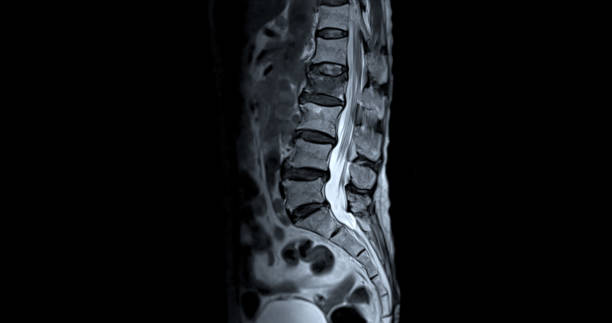

요추 전만 자세는 디스크 환자들에게 좋을 수 있지만, 과도하게 이 자세를 유지하면 문제가 발생할 수 있습니다. 연구에 따르면 과도한 요추 전만 자세는 척추 부담과 불균형을 유발하여 디스크와 관련이 있다는 결과가 나왔습니다. 더 나아가, 과도한 요추 전만 자세가 추간판 탈출증 환자에게 골반 및 하지의 부담을 증가시킬 수도 있다는 것이 밝혀졌습니다.

요추 전만 자세를 과도하게 유지하면 디스크에 더 많은 압력이 가해질 수 있어서 오히려 척추 건강에 부정적인 영향을 미칠 수 있습니다. 그러나 대체적으로 요추 전만 자세는 디스크 환자에게 도움이 되는 자세입니다.

척추의 모양은 S자형이며 요추의 중립 자세는 C자형입니다. 그러나 햄스트링이 단축되면 골반이 뒤로 넘어가게 되어 후방경사 상태가 되며, 이로 인해 요추 전만이 감소합니다. 햄스트링이 항상 단축되어 있는 상태에서 요추 전만 자세를 유지하려고 하면 척추 근육과 인대에 부하가 증가하고, 결과적으로 척추 관절의 불안정성과 통증의 원인이 될 수 있습니다.